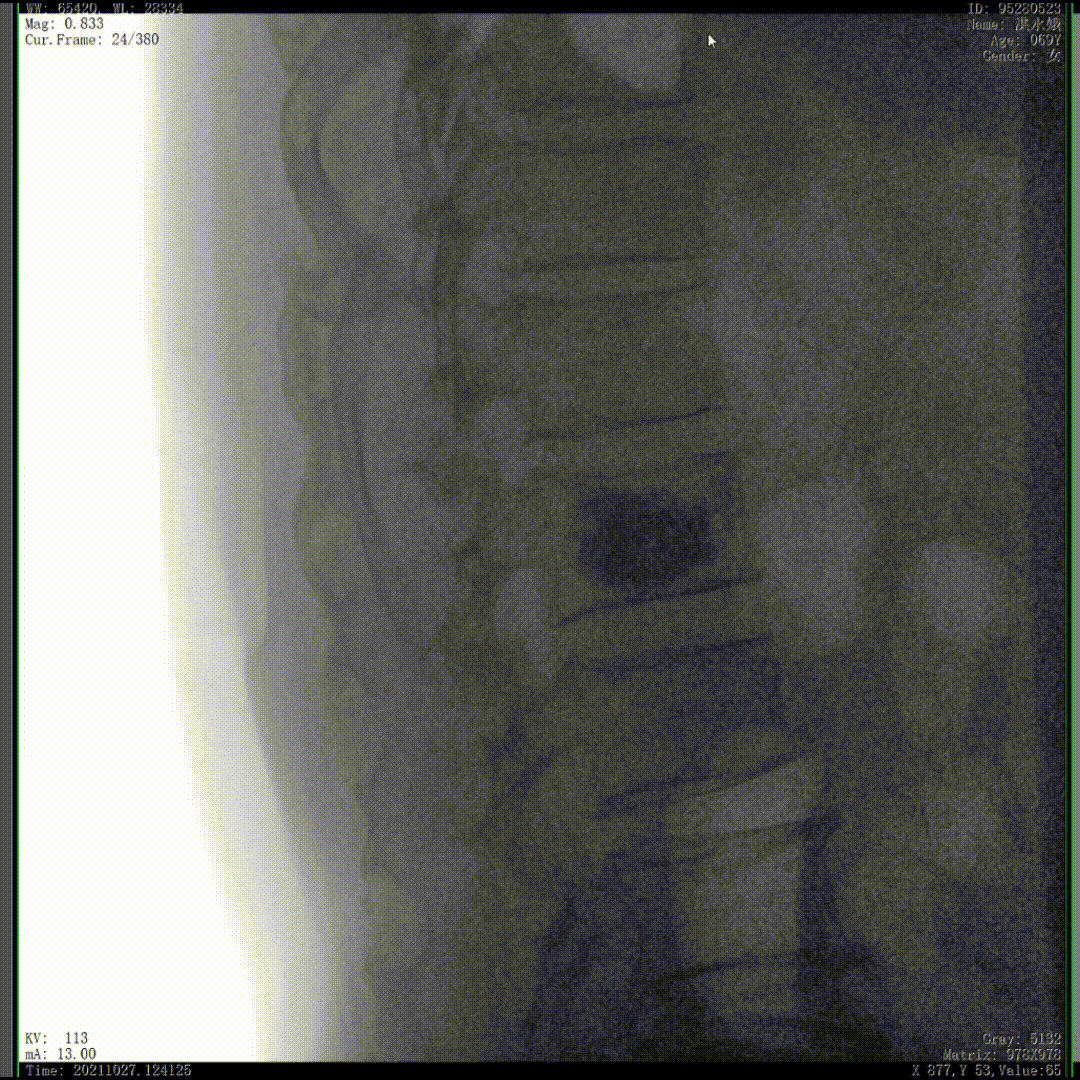

我们完成了椎体成形术以后,在二维的正侧位影像上还不能看清骨水泥的渗漏情况,通过三维影像就可以360°的观察骨水泥在椎体里到底是怎么弥散的。如果当时我们判断出来质量不好,可能还需要进行翻修,这是在二维影像上不能看到的。